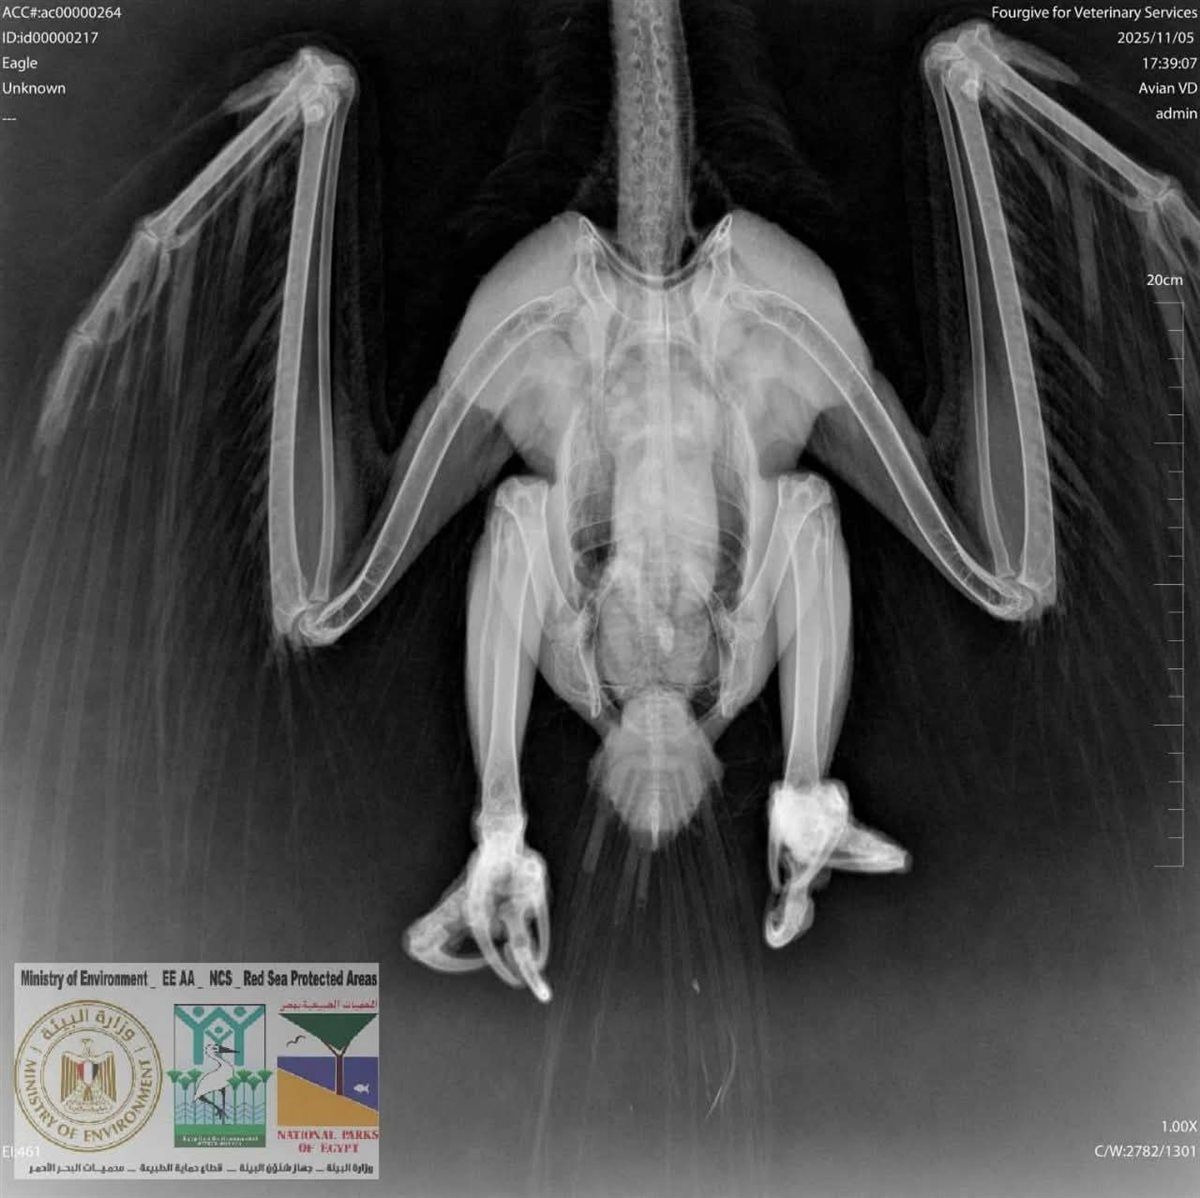

وبالتعاون مع إحدى العيادات البيطرية بمرسى علم، تم إجراء: فحوصات سريرية، وأشعة X-Ray .

وأظهرت الفحوصات عدم وجود كسور، بينما تبيّن إصابة الطائر بـ طفيليات جلدية استدعت تلقي علاجًا متخصصًا.